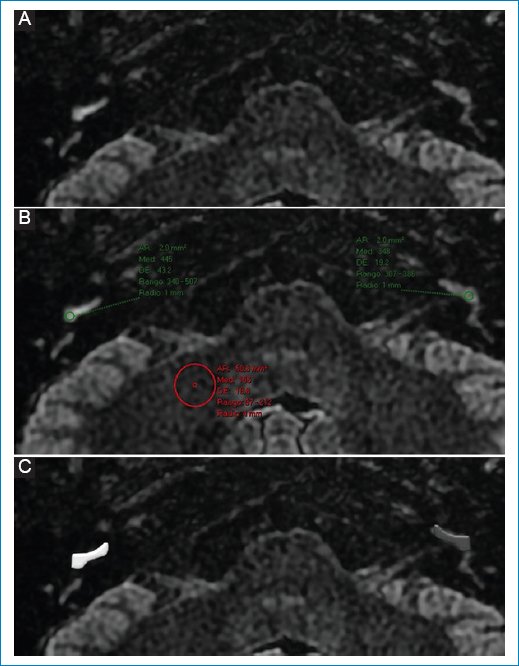

Realce perilinfático

Además del HE, numerosos estudios de imágenes han informado un mayor realce perilinfático luego del contraste intravenoso, con respecto al oído contralateral sano, en los oídos afectados de pacientes con EM (Fig. 8), que representa un deterioro de la barrera hematolaberíntica. Sin embargo, la observación de deterioro de la barrera hematolaberíntica en la RM no es exclusiva de la EM, ya que se han informado hallazgos similares en la neuritis vestibular, la pérdida auditiva neurosensorial súbita y el schwannoma vestibular, entre otros22.

Figura 8. (A y B) Realce perilinfático aumentado en el giro basal de la cóclea derecha; representación esquemática en C.

Por lo tanto, el aumento de la intensidad de la señal de la perilinfa por sí solo no es específico. No obstante, la combinación de HE (mayormente vestibular) evaluado mediante la clasificación de Bernaerts y realce de la barrera hematolaberíntica muestra una sensibilidad del 85% y una especificidad del 92% para el diagnóstico de EM. Dichos hallazgos en conjunto tienen especial relevancia en pacientes cuya clínica atípica dificulta el diagnóstico definitivo, como es el caso de la probable EM22,46,47.